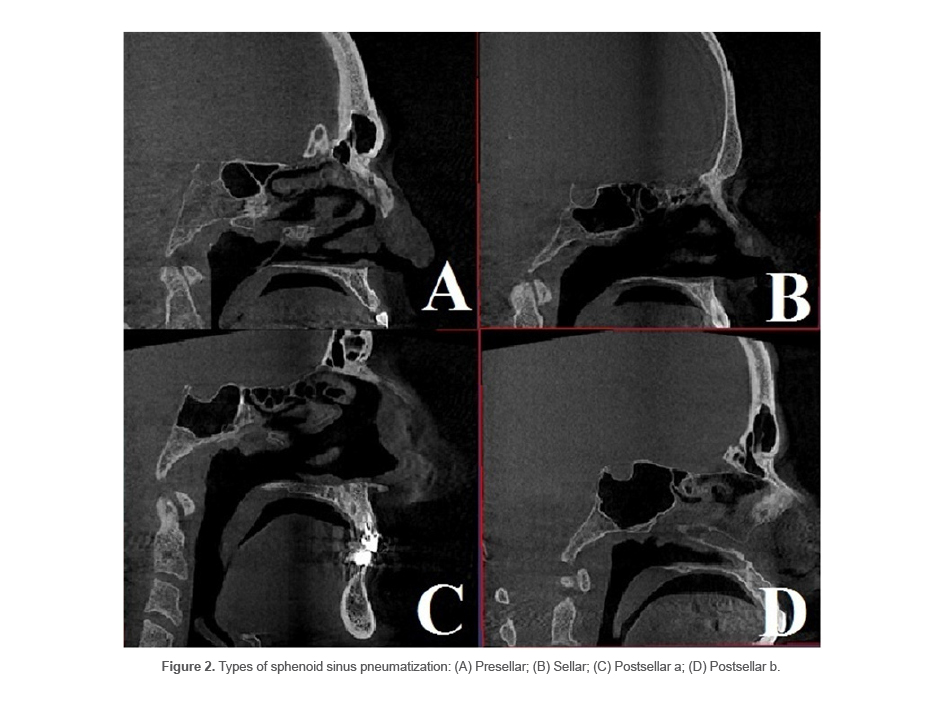

Pneumatization of ACP

ACP pneumatization was detected as extension of the sphenoid sinus into the ACP through the optic strut or anterior root in the coronal plane (14) (Figure 6).

ACP pneumatization was noted in 45% (n=135) of the patients.

ACP pneumatization was found in 45% of the patients in the present study. This rate was 33.1% in the study by Rahmati et al, (6) 25.5% in the study by Burulday et al, (14) 29.3% in the study by Şirikci et al (24) 15.3% in the study by Hewaidi et al (25) and 17.2% in the study by Kazkayasi et al (26). Considering the present results and those of Rahmati et al (6) it appears that the prevalence of ACP pneumatization in the Iranian population is higher than its average global prevalence. This finding is important since anterior clinoidectomy should be avoided or done with caution in populations where the frequency of ACP pneumatization (type 3) is high. Also, according to Burulday et al (14), rate of ACP pneumatization decreases with age, which is due to the process of sclerosis in older ages. Thus, presence/absence of ACP pneumatization should be precisely evaluated prior to this surgical procedure, especially in younger individuals in Iran, which apparently has a high prevalence of ACP pneumatization (14).

In the present study, ACP pneumatization had a significant correlation with optic canal protrusion, which was similar to the findings of Rahmati et al (6), Hewaidi et al (25), and Kazkayasi et al (26). Also, ACP pneumatization had a significant correlation with carotid canal protrusion in the present study, which was in agreement with the findings of Hewaidi et al (25). However, Rahamti et al (6) and Kazkayasi et al (26) did not find a significant correlation between ACP pneumatization and carotid canal protrusion. But, it should be noted that our sample size was larger than that of Rahmati et al (6).

Figure 6. ACP pneumatization by the sphenoid sinus at both sides.